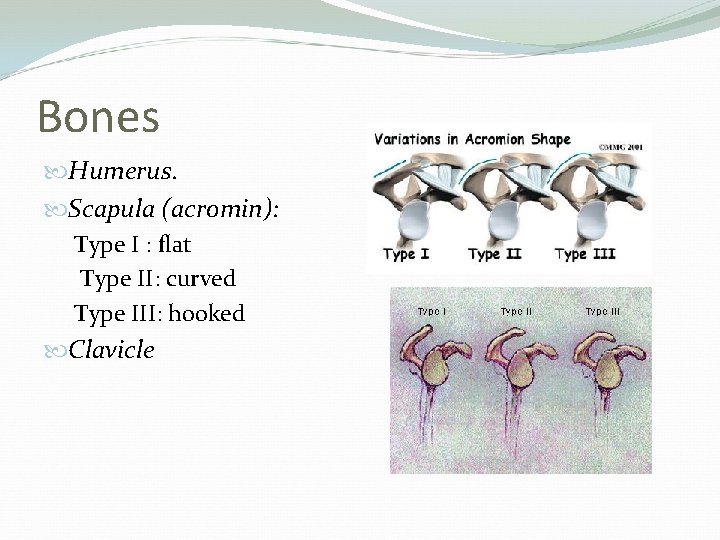

Bones Humerus. Scapula (acromin): Type I : flat Type II: curved Type III: hooked Clavicle